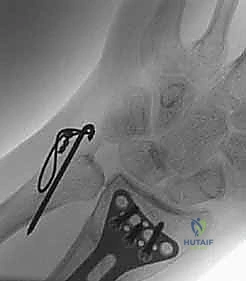

ثانياً: العلاج الجراحي (Surgical Intervention)

متى يقرر الدكتور هطيف ضرورة التدخل الجراحي؟

1. عدم الاستقرار (Instability): إذا كان المفصل الزندي الكعبري البعيد (DRUJ) غير مستقر بعد تثبيت كسر الكعبرة.

2. الانزياح (Displacement): إذا كان الكسر في قاعدة الناتئ الإبري منزاحًا بأكثر من 2 ملم.

3. الكسور المفصلية: أي كسر يخل بتطابق السطح المفصلي لرأس الزند.

4. الكسور المفتتة: في الجزء الكردوسي التي تؤدي إلى قصر عظم الزند.

5. الكسور المفتوحة (Open Fractures): حيث يبرز العظم من الجلد، وتتطلب جراحة طارئة لتنظيف الجرح وتثبيت الكسر لمنع العدوى.

خطوات التدخل الجراحي الدقيق مع الأستاذ الدكتور محمد هطيف

تُعد جراحات المعصم والزند من الجراحات الدقيقة التي تتطلب مهارة عالية، وهو المجال الذي يتفوق فيه الأستاذ الدكتور محمد هطيف بفضل استخدامه لتقنيات الجراحة المجهرية (Microsurgery) والأدوات الجراحية ذات التقنية العالية.

1. التخطيط ما قبل الجراحة (Pre-operative Planning)

يقوم الدكتور هطيف بدراسة الأشعة المقطعية ثلاثية الأبعاد بدقة، ويختار نوع وحجم الصفائح المعدنية (Plates) والمسامير (Screws) المناسبة لكل مريض بناءً على حجم العظم ونوع الكسر.